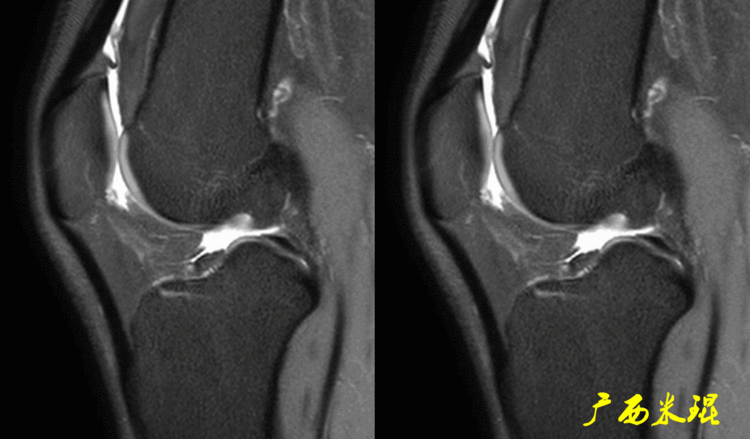

一、半月板损伤MR诊断的思路1、单纯就半月板改变诊断半月板损伤半月板信号(3级信号)及形态的异常是诊断半月板损伤最为直接的征象,当我们在阅片当中发现这些征象,一般情况下都能够确诊半月板损伤,下面这张MR,我们发现外侧半月板后角出现3级信号,所以能够确定其半月板损伤。

2、从发病机制诊断半月板损伤并不是每个病人都能够这么清晰的显示半月板的信号改变,同样这张MR,我们发现患者出现明显的对吻征,対吻征是诊断ACL损伤的重要体征,说明病人受伤的同时膝关节扭转严重,甚至出现轴移,这种情况下(损伤/发病机制)外侧半月板后根极其容易受伤,我们再认真的阅看其他截面,就很容易找到半月板损伤的佐证。